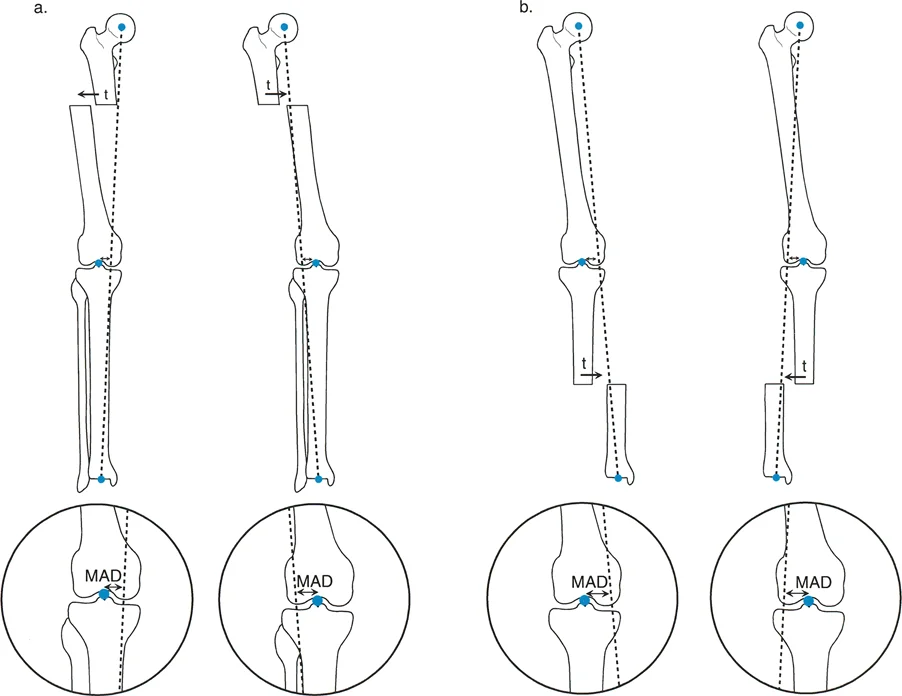

مفهوم الانزياح (Translation Deformity)

يشير "تشوه الانزياح" إلى إزاحة أو تحرك جانبي (ad latus) لجزء من العظم بالنسبة للجزء الآخر. تخيل أن عظمة طويلة قد انكسرت، وبدلاً من أن تلتئم أطراف الكسر بشكل مباشر ومتقابل، تحرك أحد الأجزاء جانباً، بحيث لم تعد أطراف الكسر متطابقة تماماً. هذه الإزاحة تكون عادةً عمودية على المحور الطولي للعظم.

الفرق بين الانزياح والانحراف الزاوي (Angulation)

* الانزياح (Translation): هو حركة جانبية أو إزاحة، حيث تتحرك أطراف العظم بعيداً عن بعضها البعض في اتجاه جانبي، مما قد يؤدي إلى فقدان التلامس بينها.

* الانحراف الزاوي (Angulation): هو انحناء في العظم، حيث تظل أطراف العظم متلامسة ولكنها لا تكون مستقيمة، بل تشكل زاوية.

في بعض الحالات، قد يحدث الانزياح والانحراف الزاوي معاً، أو قد يؤدي أحدهما إلى الآخر. على سبيل المثال، يمكن أن تؤدي زاويتان متقابلتان في نفس مستوى العظم إلى تأثير صافٍ يتمثل في الانزياح.

7. تأثير الانزياح على محور الحمل الميكانيكي (MAD)

تشوهات الانزياح، خاصة في عظم الفخذ أو الساق، يمكن أن تؤدي إلى تغيير في "محور الحمل الميكانيكي" (Mechanical Axis Deviation - MAD). هذا يعني أن القوى التي تمر عبر المفصل (مثل الركبة) لا تتوزع بالتساوي، مما قد يؤدي إلى:

5. قياس محور الحمل الميكانيكي (Mechanical Axis Deviation - MAD)

يُعد قياس محور الحمل الميكانيكي أمراً حاسماً، خاصة في تشوهات عظم الفخذ والساق التي تؤثر على مفصل الركبة. يتم ذلك باستخدام صور الأشعة السينية الطويلة التي تشمل الورك والركبة والكاحل. يساعد هذا القياس في:

* تقييم تأثير الانزياح على المفصل: تحديد مدى تأثير الانزياح على توزيع الضغط في الركبة.

* تخطيط التصحيح الجراحي: توجيه الجراح لتصحيح الانزياح بطريقة تعيد المحاذاة الميكانيكية الطبيعية.